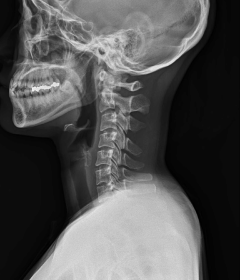

정상적인 목뼈는 C자 형태의 굴곡을 지니고 있습니다. 이를 "전만"이라고 합니다.

그러나 잘못된 자세나 생활습관으로 인해 목뼈의 모양이 일자로 곧게 뻗은 경우는 '일자목 증후군'이라고 하며, 더 심한 경우는 반대 C자 형태 즉, 역 C자 형태의 목을 '거북목 증후군' 또는 '자라목 증후군'이라고 합니다. 이는 의학적으로 경추 후만증으로 일컫습니다.

정상목

거북목

일자목